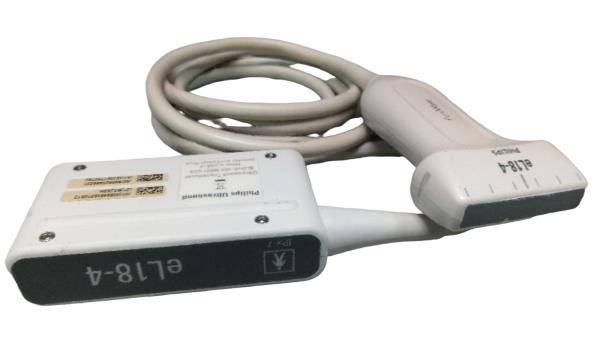

The laptop ultrasound scanner

utilizes state-of-the-art technology to provide clear and accurate imaging, essential for diagnosing various medical conditions. With both transvaginal and convex probes, it caters to a wide range of examinations. This versatility ensures healthcare professionals can perform different types of scans with a single device, making it incredibly efficient. Moreover, the scanner’s lightweight design allows for easy transport, which is particularly beneficial in emergency medical situations.